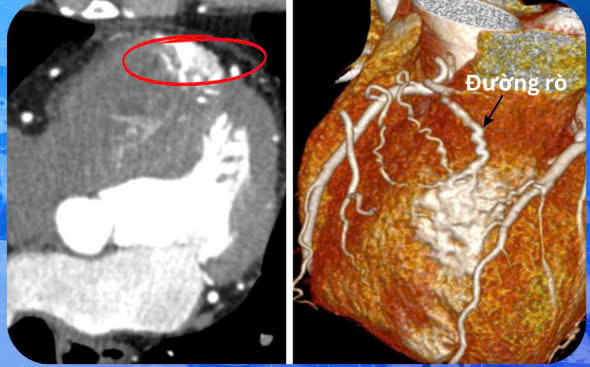

Tại bệnh viện, bệnh nhân được chỉ định thực hiện các xét nghiệm và cận lâm sàng cần thiết để đánh giá tình trạng sức khoẻ. Kết quả cho thấy: nhịp tim đều, tiếng T1, T2 rõ, không ghi nhận tiếng thổi, nhịp xoang đều, tần số tim 60 lần/phút. Trục điện tim vô định, sóng T âm ở chuyển đạo aVL, xuất hiện ngoại tâm thu rải rác, số lượng ít. Hở nhẹ van hai lá và van động mạch chủ. Thành thất trái dày nhẹ, buồng thất không giãn. Chức năng co bóp của thất trái và thất phải bình thường. Rối loạn chức năng tâm trương thất trái mức độ nhẹ (độ I). Tăng nhẹ áp lực động mạch phổi. Phát hiện rò động mạch vành từ nhánh nón của động mạch vành phải (RCA) vào tâm thất phải. Biến thể giải phẫu có nhánh động mạch trung gian (Ramus). Mảng xơ vữa vôi hóa ở nhánh LAD1 gây hẹp 36% (chỉ số vôi hóa Agatston 103 điểm).

Dựa vào kết quả lâm sàng và cận lâm sàng đã thực hiện, bệnh nhân S. được chẩn đoán bị dò động mạch vành, xơ vữa động mạch vành, động mạch cảnh, theo dõi COPD. Bác sĩ đã kê đơn điều trị nội khoa cho bệnh nhân.